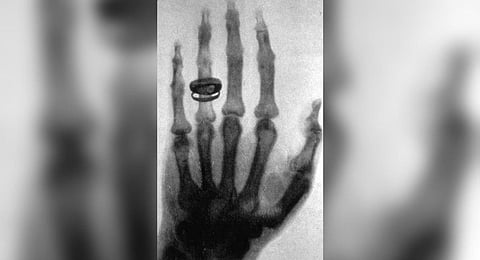

One of Roentgen’s first experiments late in 1895 was a film of the hand of his wife, Anna Bertha, which showed bones of her hand and their wedding ring. Interestingly, the first use of X-rays was for industrial applications, as Roentgen produced a radiograph of a set of weights in a box to show his colleagues.